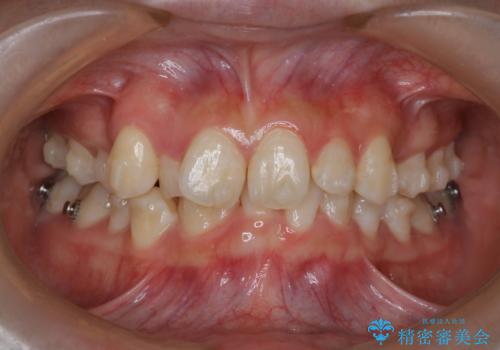

- 20代女性

- 1年9ヶ月

- 前歯のガタガタを主訴に来院されました。

抜歯を行い、インビザラインにて治療を完了しております。